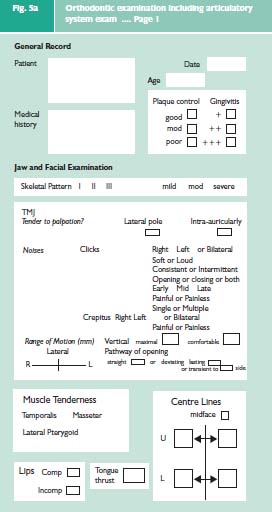

The three elements of an examination of the articulator system2 can easily be incorporated into an orthodontic examination protocol (Fig. 5a–c). This comprehensive examination is divided into two main parts. The jaw and facial examination will record the pattern of the skeletal bases and the facial symmetry, the condition of the TMJs and mandibular muscles, and the soft tissue characteristics. The dental and occlusal examination will record the position of the teeth and their occlusal contacts.